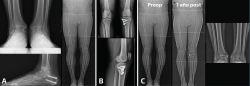

Figura 1. Paciente con genu varo ya operado por pie plano valgo con coalición tarsal y tobillo doloroso. A: se realizó una osteotomía varizante de calcáneo; B: la mejoría después de la cirugía del retropié fue insuficiente y se realizó una osteotomía valguizante de tibia proximal; C: imágenes radiológicas al año de la cirugía. El paciente se encontraba asintomático de su tobillo, que había mejorado también en apariencia radiológica.